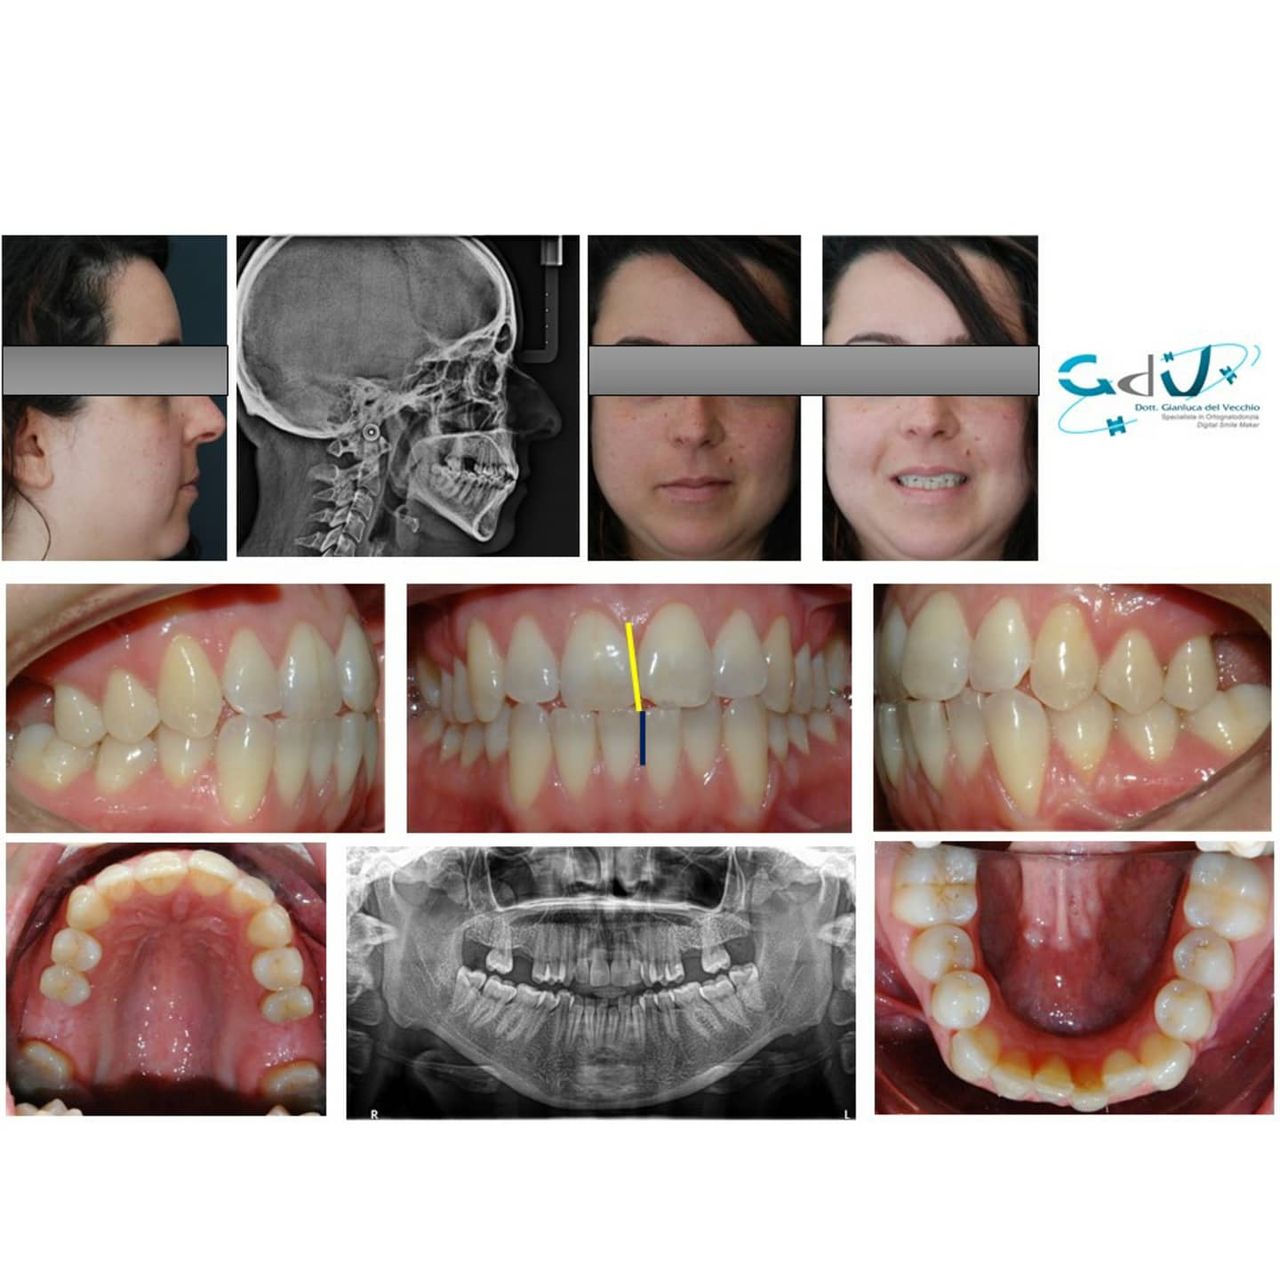

Il dottor Gianluca del Vecchio si occupa esclusivamente di ortognatodonzia, grazie anche alla collaborazione multidisciplinare di una équipe davvero entusiasmante e all’utilizzo di strumenti diagnostici e terapeutici all’avanguardia in ortognatodonzia. Particolare è la sua capacità di condurre i giovani pazienti ad affrontare, nella massima sicurezza emotiva e clinica, qualsiasi eventuale condizione di dolore derivante, ad esempio, da carie o da altre patologie, ma soprattutto di risolvere tutte quelle condizioni di “denti storti”, così spesso causa di disagio psicologico o di fenomeni deprecabili, quale il bullismo.

L’ortognatodonzia è la disciplina che si occupa dell’ortopedia delle ossa mascellari, interviene sulla crescita delle stesse modificando la posizione dei denti secondo quanto necessario. Così la pedodonzia, la seconda disciplina che si occupa, ma in modo esclusivo, dei bambini, affronta tutte le classiche patologie del cavo orale, quando i pazienti sono in età scolare.

Queste le ragioni che consentono di trattare le malocclusioni, sia dei bambini che degli adulti, con protocolli scientificamente validati come i più veloci, affidabili e confortevoli.

Foto e video